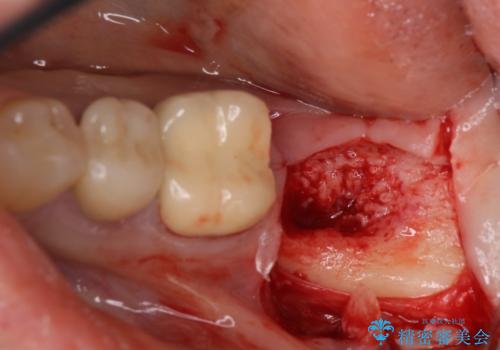

インプラント埋入にあたり、歯槽骨での炎症が広範囲であったことから、事前に骨造成を行いました。

歯槽骨の高さや幅を回復することができ、望ましい位置にインプラントを埋入することができました。